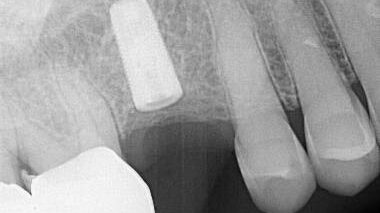

A Type V Abutment and Abutment Screw Recovery Case created by Prior Eccentric Free Hand Drilling – 0041

This case showcases an example of A Type V Abutment and Abutment Screw Recovery Case created by Prior Eccentric Free Hand Drilling.

A Diagnostic and Treatment Algorithm for Fractured Implant Screw Retrieval: Organizing for a Safe Recovery to Preserve Implant Integrity.

This implant case exemplifies a Failed Fractured Abutment Screw Recovery attempt with a Salvin screw recovery kit.